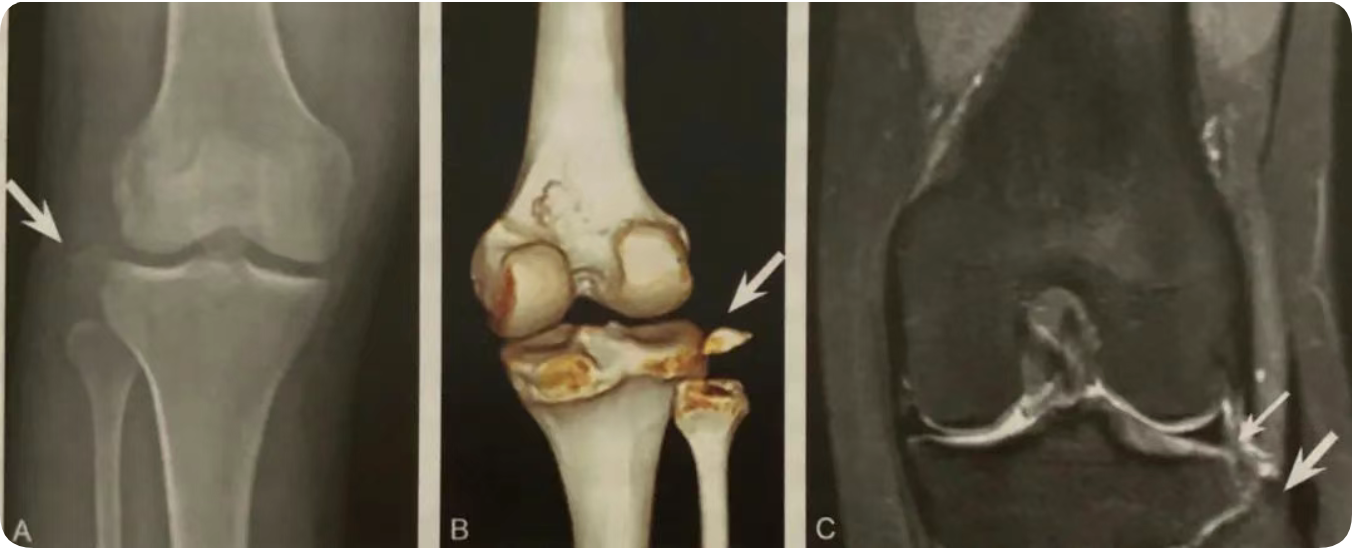

1. 腓骨小头撕脱性骨折的直接征象,弓形复合体和后外侧角损伤的间接征象;

2. 在膝关节X线前后位或 CT、MRI 冠状位观察,表现为近端腓骨小头或腓骨茎突撕脱性骨折,碎骨片呈弓形;

3. X 线片或 CT 观察到弓形征后,须行 MRI 检查,观察弓形复合体及后外侧角的完整性;

4. 少数后外侧角损伤合并腓总神经及胭动静脉损伤。